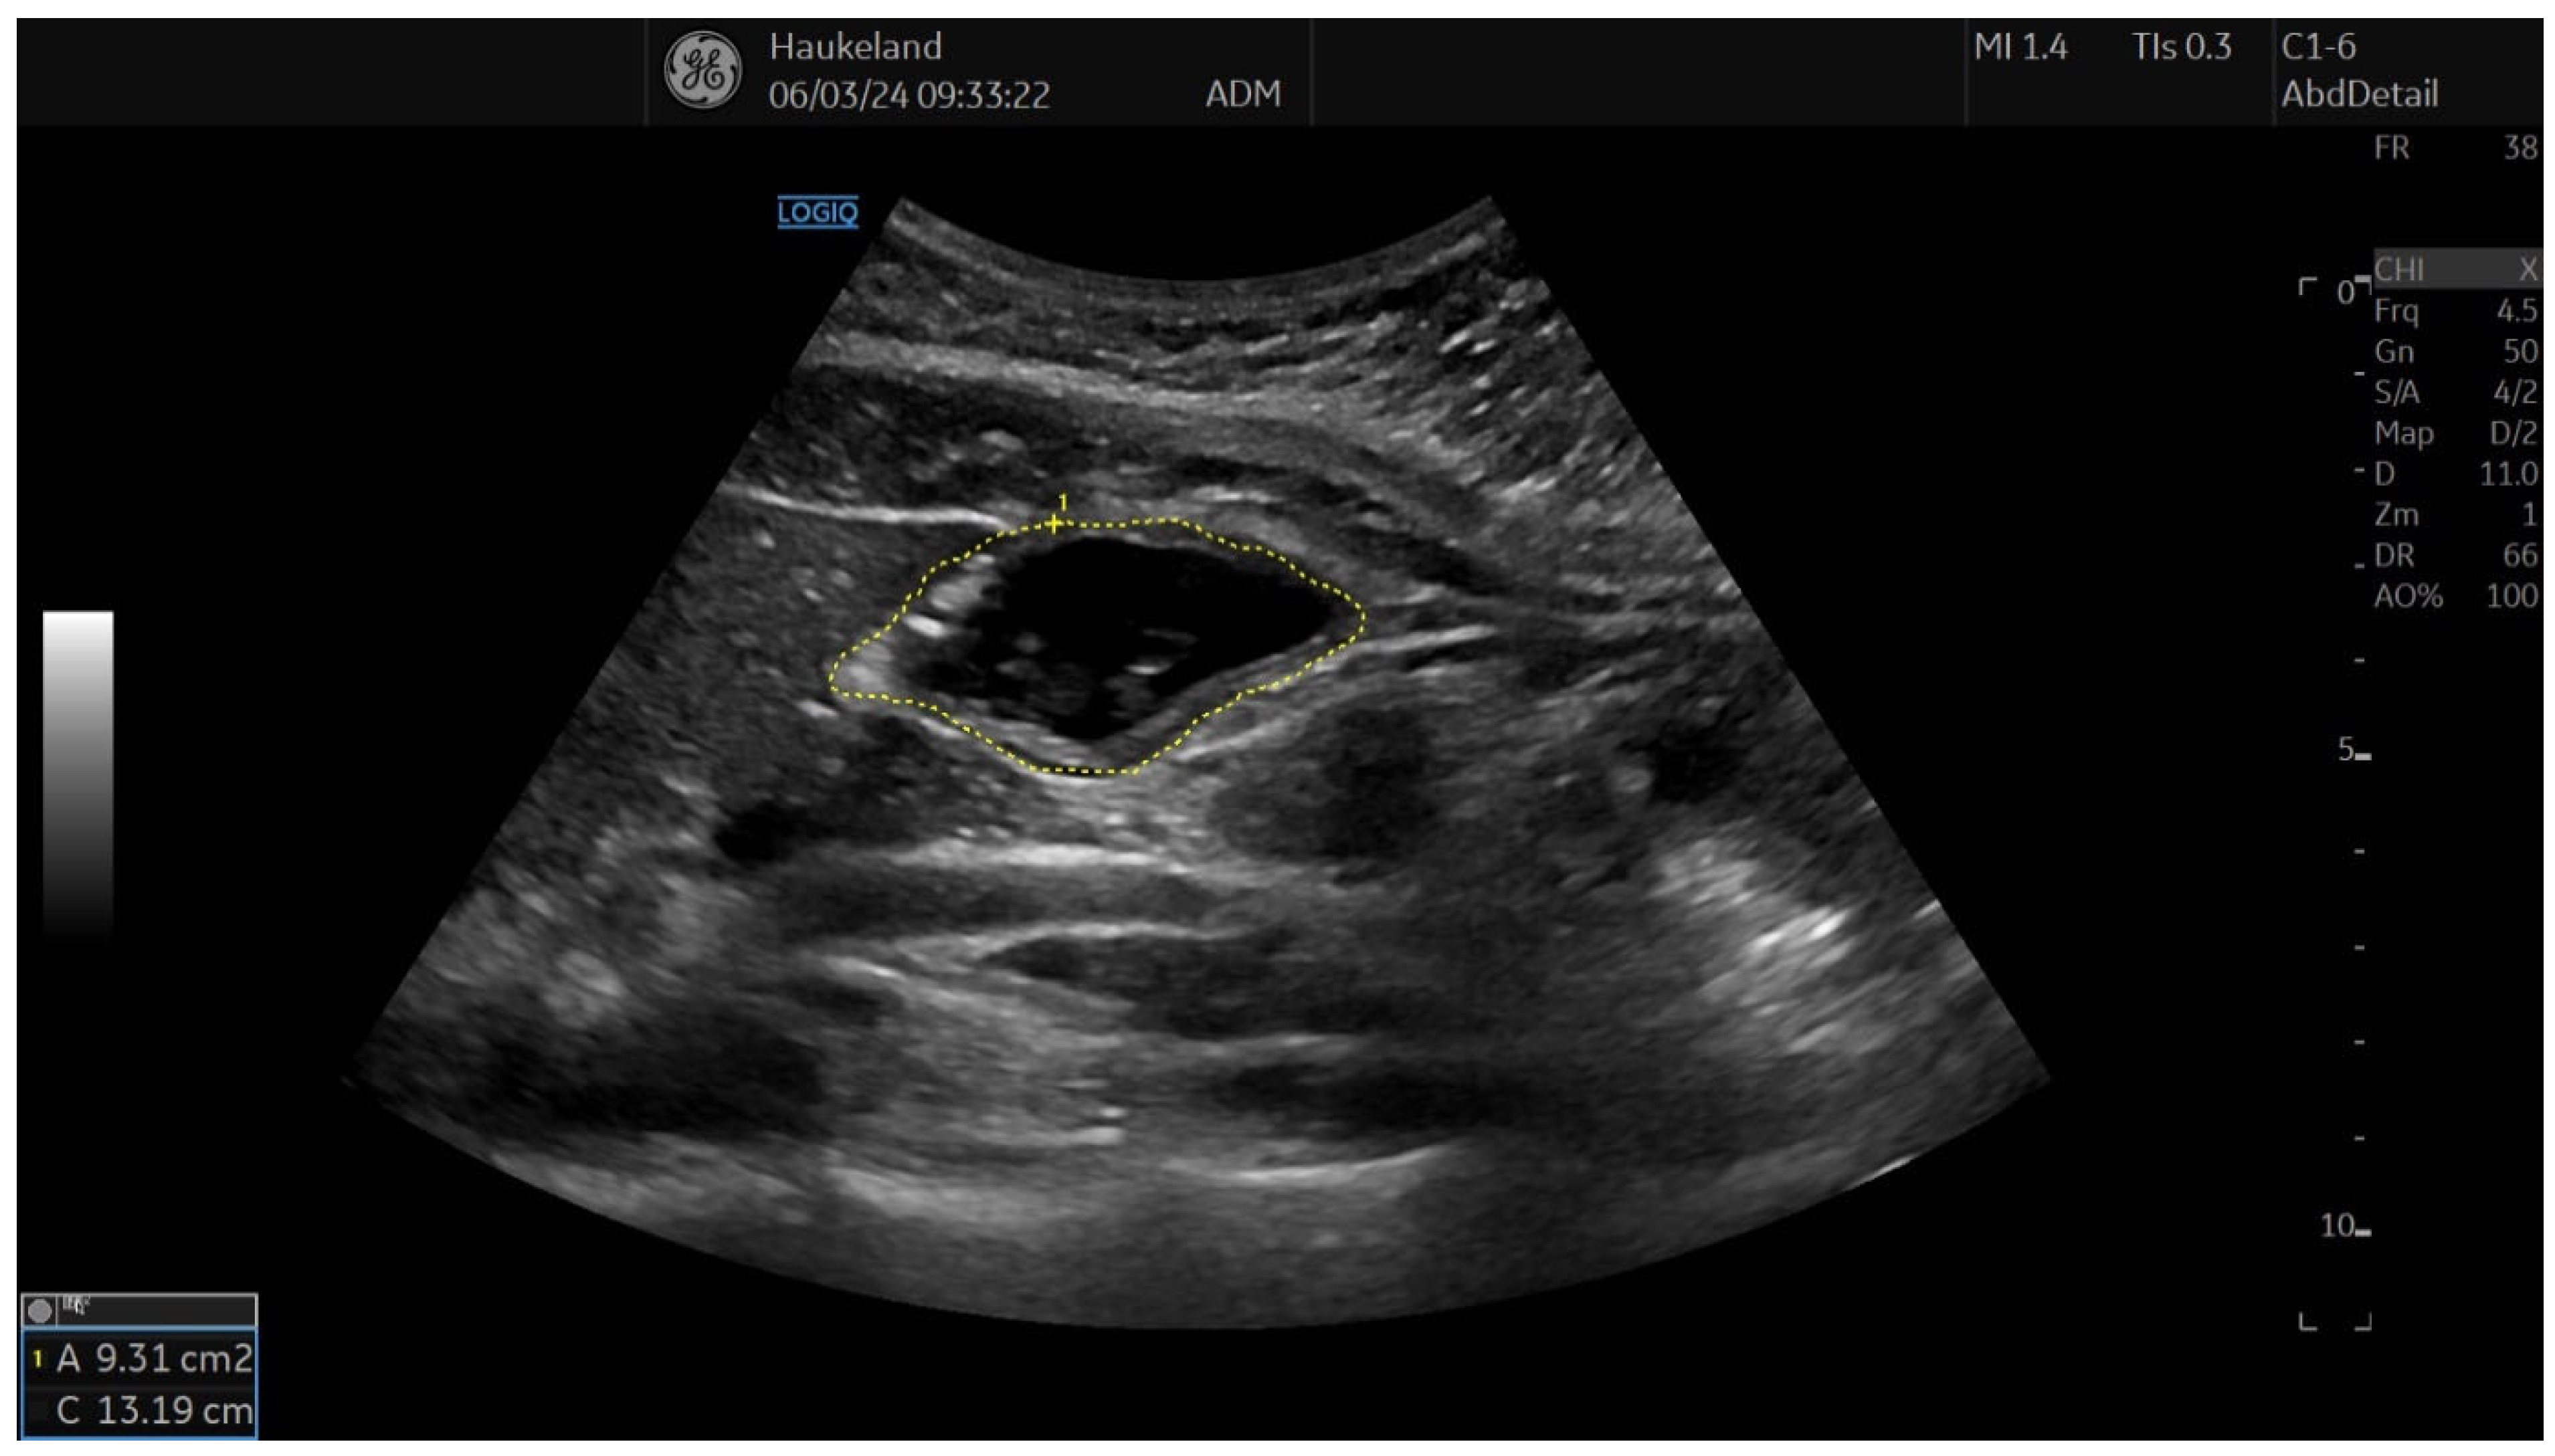

Figure 3. This image shows a measurement of proximal gastric area (PGA) using 2D-US in sagittal section, and this is used to assess gastric accommodation. PGA was obtained by placing the transducer longitudinally under the left subcostal margin and tilting it cranially in the long axial direction. Internal landmarks to look for were the left kidney in the longitudinal projection, the left lobe of the liver, and the tail of the pancreas. PGA was calculated by tracing along the luminal echogenic surface, which corresponded to the interface between the gastric liquid and the mucosa of the gastric wall. This was performed from the top margin of the fundus to 7 cm inferiorly along the axis of the proximal stomach. This image was taken after meat soup ingestion as part of the ultrasound meal accommodation test (UMAT) that is regularly performed at Haukeland University Hospital, Bergen, Norway.

The most common method applied to assess proximal gastric accommodation was by assessing changes in proximal gastric area (PGA) and maximal proximal gastric diameter (MPGD). Changes in PGA and MPGD after meal ingestion were used as indirect measurements of proximal gastric volume changes, thus reflecting gastric accommodation. To obtain PGA, the transducer was placed in the epigastrium longitudinally under the left subcostal margin and tilted cranially in the long axial direction [11,12,18,22]. This allowed for a visualization of a sagittal section of the proximal stomach, and internal landmarks were the left kidney in the longitudinal projection, the left lobe of the liver, and the tail of the pancreas [11,12,18,22]. On the sagittal section, PGA was calculated by tracing along the luminal echogenic surface, which corresponded to the interface between the gastric liquid and the mucosa of the gastric wall (Figure 3) [11,12]. This was performed from the top margin of the fundus to 7 cm inferiorly along the axis of the proximal stomach (Figure 3) [11,12,18,22]. MPGD was obtained from an oblique frontal section (transverse section), which was achieved by rotating the probe 90° clockwise and tilting it cranially in the short axial direction [11,12,18,22]. The landmarks to look for in the transverse section were the left hemidiaphragm, the top margin of the fundus, and the liver parenchyma [11,12,18,22]. The diameter was measured within the 7 cm long axis of the proximal stomach (Figure 4) [18,22].